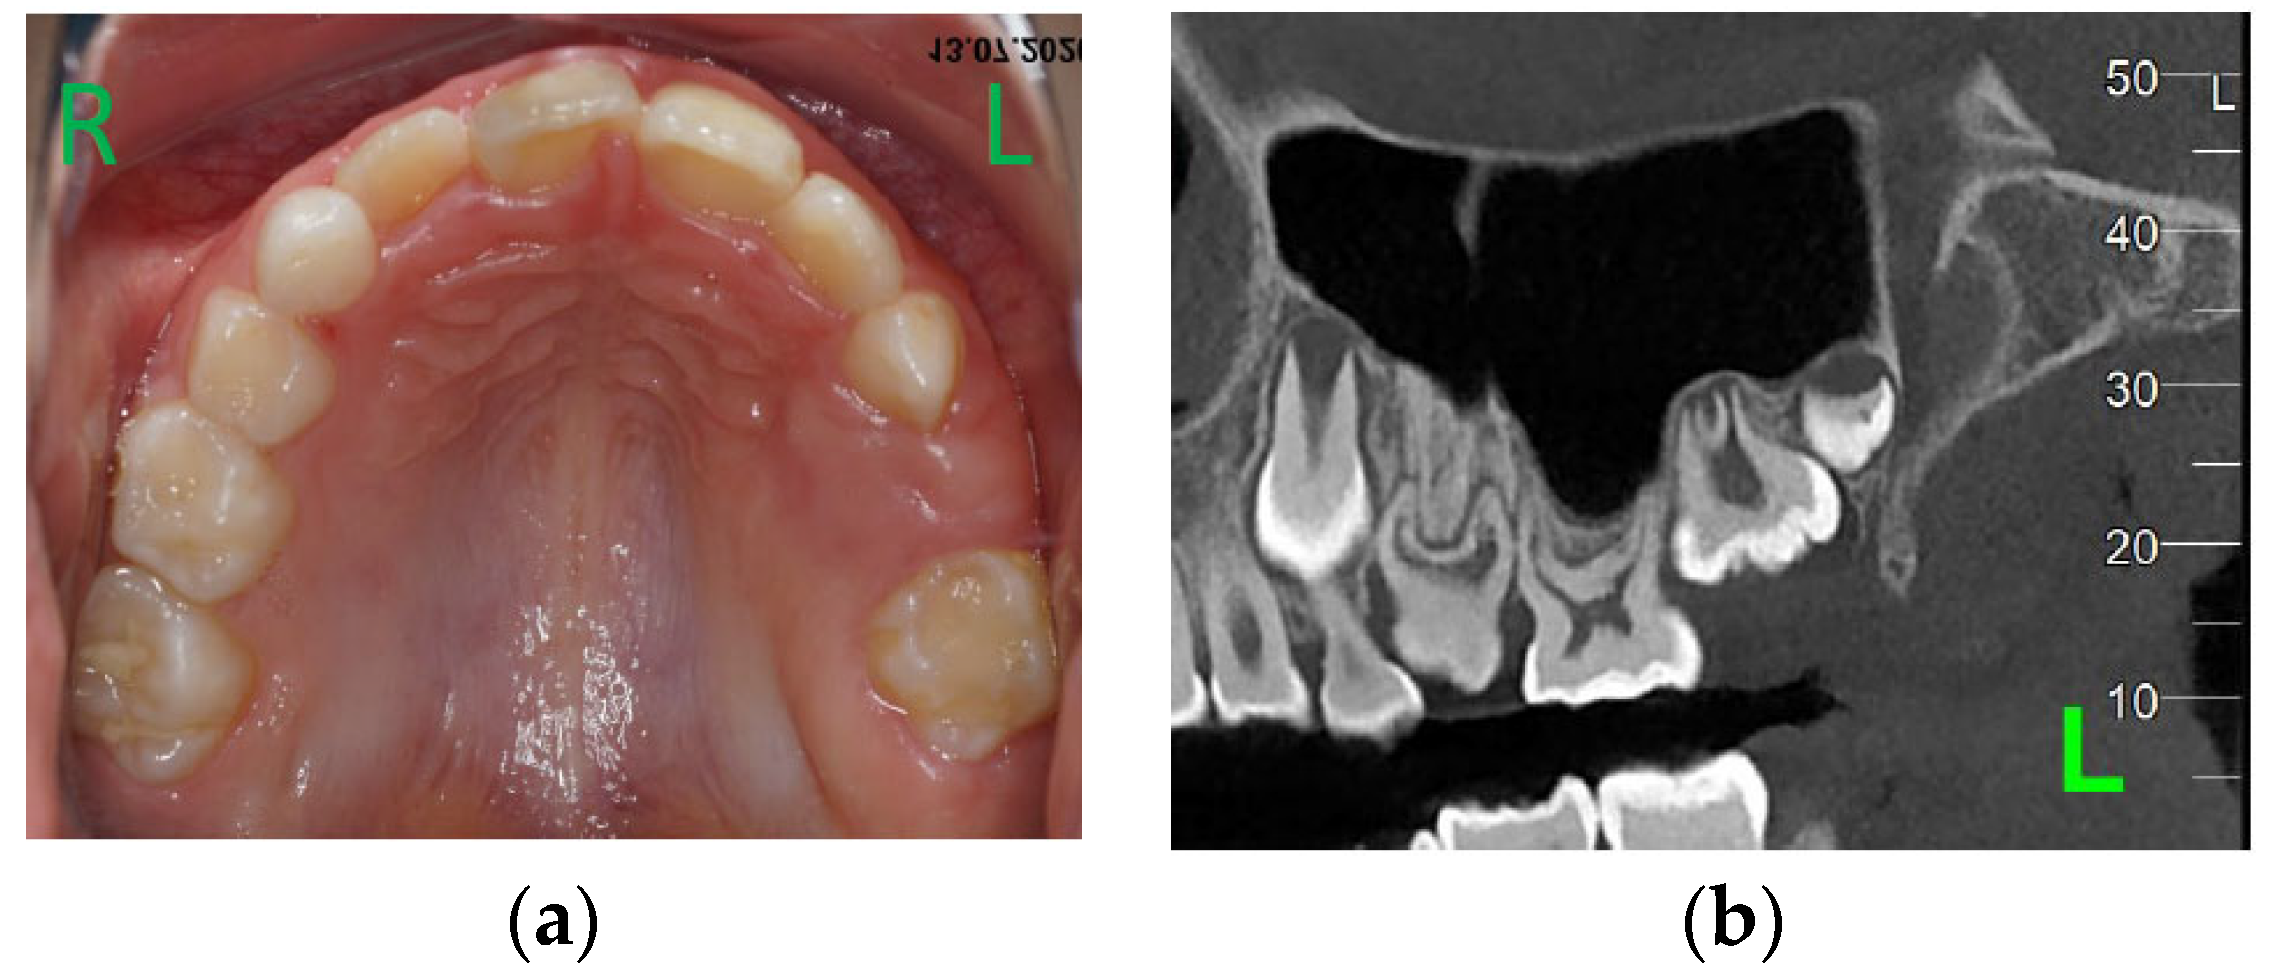

At the age of 9 y and 7 m, 26 was still not on the arch (Figure 4a). A cone beam computed tomography (CBCT) examination was performed. Agenesis of 24 and 25 became certain (Figure 4b), and no areas of ankylose in teeth with eruption failure were found. A decision was taken to remove 63 in order to favor the eruption of mechanically impacted 64, but extraction was postponed at the family’s request.

Figure 4.

Age of 9 y and 7 m. (a) Occlusal view of the upper arch; (b) CBCT confirmed agenesis of 24, 25, and impaction of 64.